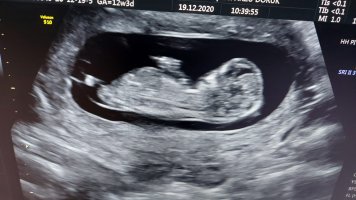

Benim bebeğime de bakar mısınız 12 hafta 3 günlük

136,1 KB · Görüntüleme: 1.325

160,7 KB · Görüntüleme: 390